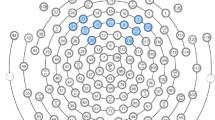

To calculate power spectral density (PSD) for the gamma-band frequency range (35–54.99 Hz) we used the Batch EEG Automated Processing Platform, BEAPP [60] in MATLAB 2021a, consisting of: (1) format the MFF file for Matlab; (2) band-pass filter 1–100 Hz; (3) down sampling from 500 to 250 Hz; (4) implementation of the Harvard Automated Preprocessing Pipeline for EEG (HAPPE) module for artifact detection and rejection [61], including removal of 60 Hz line noise, rejection of bad channels, wavelet enhanced thresholding, Independent Component Analysis (ICA) with automated component rejection, bad channel interpolation, and re-referencing to average; (5) segmentation of the continuous file into 1 s epochs (each epoch consisted of one three-syllabic pseudoword); (6) rejection of bad segments (± 40 μV); (7) calculation of the PSD using Hanning window on clean segments. We focused on the low gamma frequency band (35–54.99 Hz) to avoid potential effects of 60 Hz line noise and the notch filter used for its removal. A total of nine regions of interest (ROIs) were used for the analysis as depicted in Fig. 2. PSD was calculated for each electrode, averaged within each ROI, and normalized with natural logarithm transformation.

EEG montage with channels indicated. Channel numbers for regions are (1) frontal left (20, 23, 24, 27, 28), (2) frontal midline (5, 6, 11, 12, 16), (3) frontal right (3, 117, 118, 123, 124), (4) central left (35, 36, 41, 42, 47), (5) central midline (7, 31, 55, 80, 106), (6) central right (93, 98, 103, 104, 110), (7) posterior left (51, 52, 59, 60, 65), (8) posterior midline (62, 71, 72, 76), (9) posterior right (85, 90, 91, 92, 97)